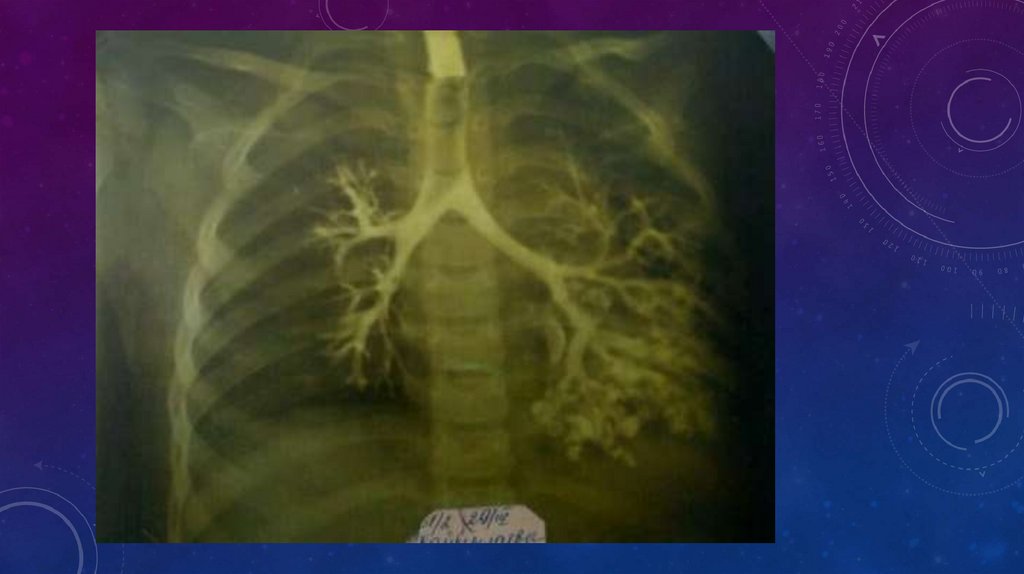

• Бронхографию, особенно у детей, следует выполнять водорастворимыми контрастными веществами,

поскольку они всасываются и быстро выводятся из организма. Масляное контрастное вещество (йодолипол),

наоборот, может длительно задерживаться в легочной ткани не только в пораженных, но и в здоровых

участках легкого.

• Наиболее целесообразна методика бронхографии над наркозом с искусственной вентиляцией легких.

Дыхание осуществляют через интубационную трубку или с помощью дыхательного бронхоскопа.

Контрастное вещество вводят во время апноэ по катетеру, который постепенно подтягивают от

нижнедолевого к верхнедолевому бронху. Первый снимок производят в положении на исследуемом боку,

второй — в положении на спине. После тщательной аспирации контрастного вещества из бронхов

приступают к контрастированию второго легкого.

• Для правильной интерпретации бронхограмм необходимо ориентироваться в сегментарном строении

легкого и картине разветвлений бронхиального дерева. Наиболее информативны бронхограммы в боковых

проекциях, на которых хорошо видны все долевые и сегментарные бронхи. В норме бронхи заполняются

контрастным веществом, вплоть до терминальных разветвлений, при этом они равномерно суживаются к

периферии и имеют ровные, гладкие контуры. При бронхоэктазии на бронхограммах выявляются

деформации бронхиального дерева: цилиндрические и мешковидные расширения бронхиальных стволов,

без контрастирования терминальных отделов. В зонах ателектаза и склероза бронхи особенно

деформированы и сближены.